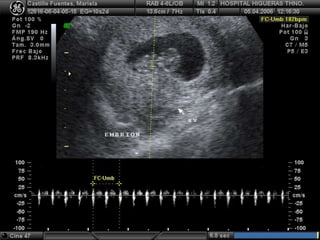

Ductus Venoso:

 Pequeña porción de la vena

umbilical antes de su llegada al

corazón.

 La alteración en la forma de las

ondas obtenidas del flujo de esta

estructura anatómica fetal se

considera anormal y sugiere

riesgo elevado de Síndrome de

Down o Cardiopatía Congénita.

 Detección reportada: 80-90%

(Down); detección variable en

Cardiopatías.